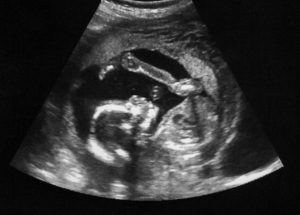

Figure. Ultrasound with pregnancy obstetric of fetus